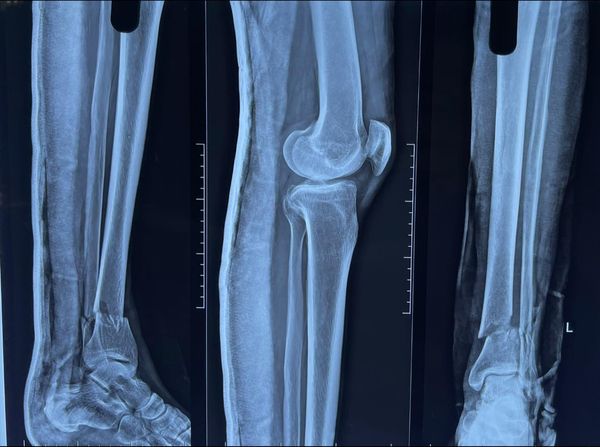

Neck of Femur Fractures

Most neck of femur fractures are treated with partial or total jointreplacement surgeries. however doing so limits active lifestyle in younger individuals. Especially in the Indian system of living. that is why it’s important to take such fractures as surgical emergencies in young people like this 43 year old woman and treat them with screw […]